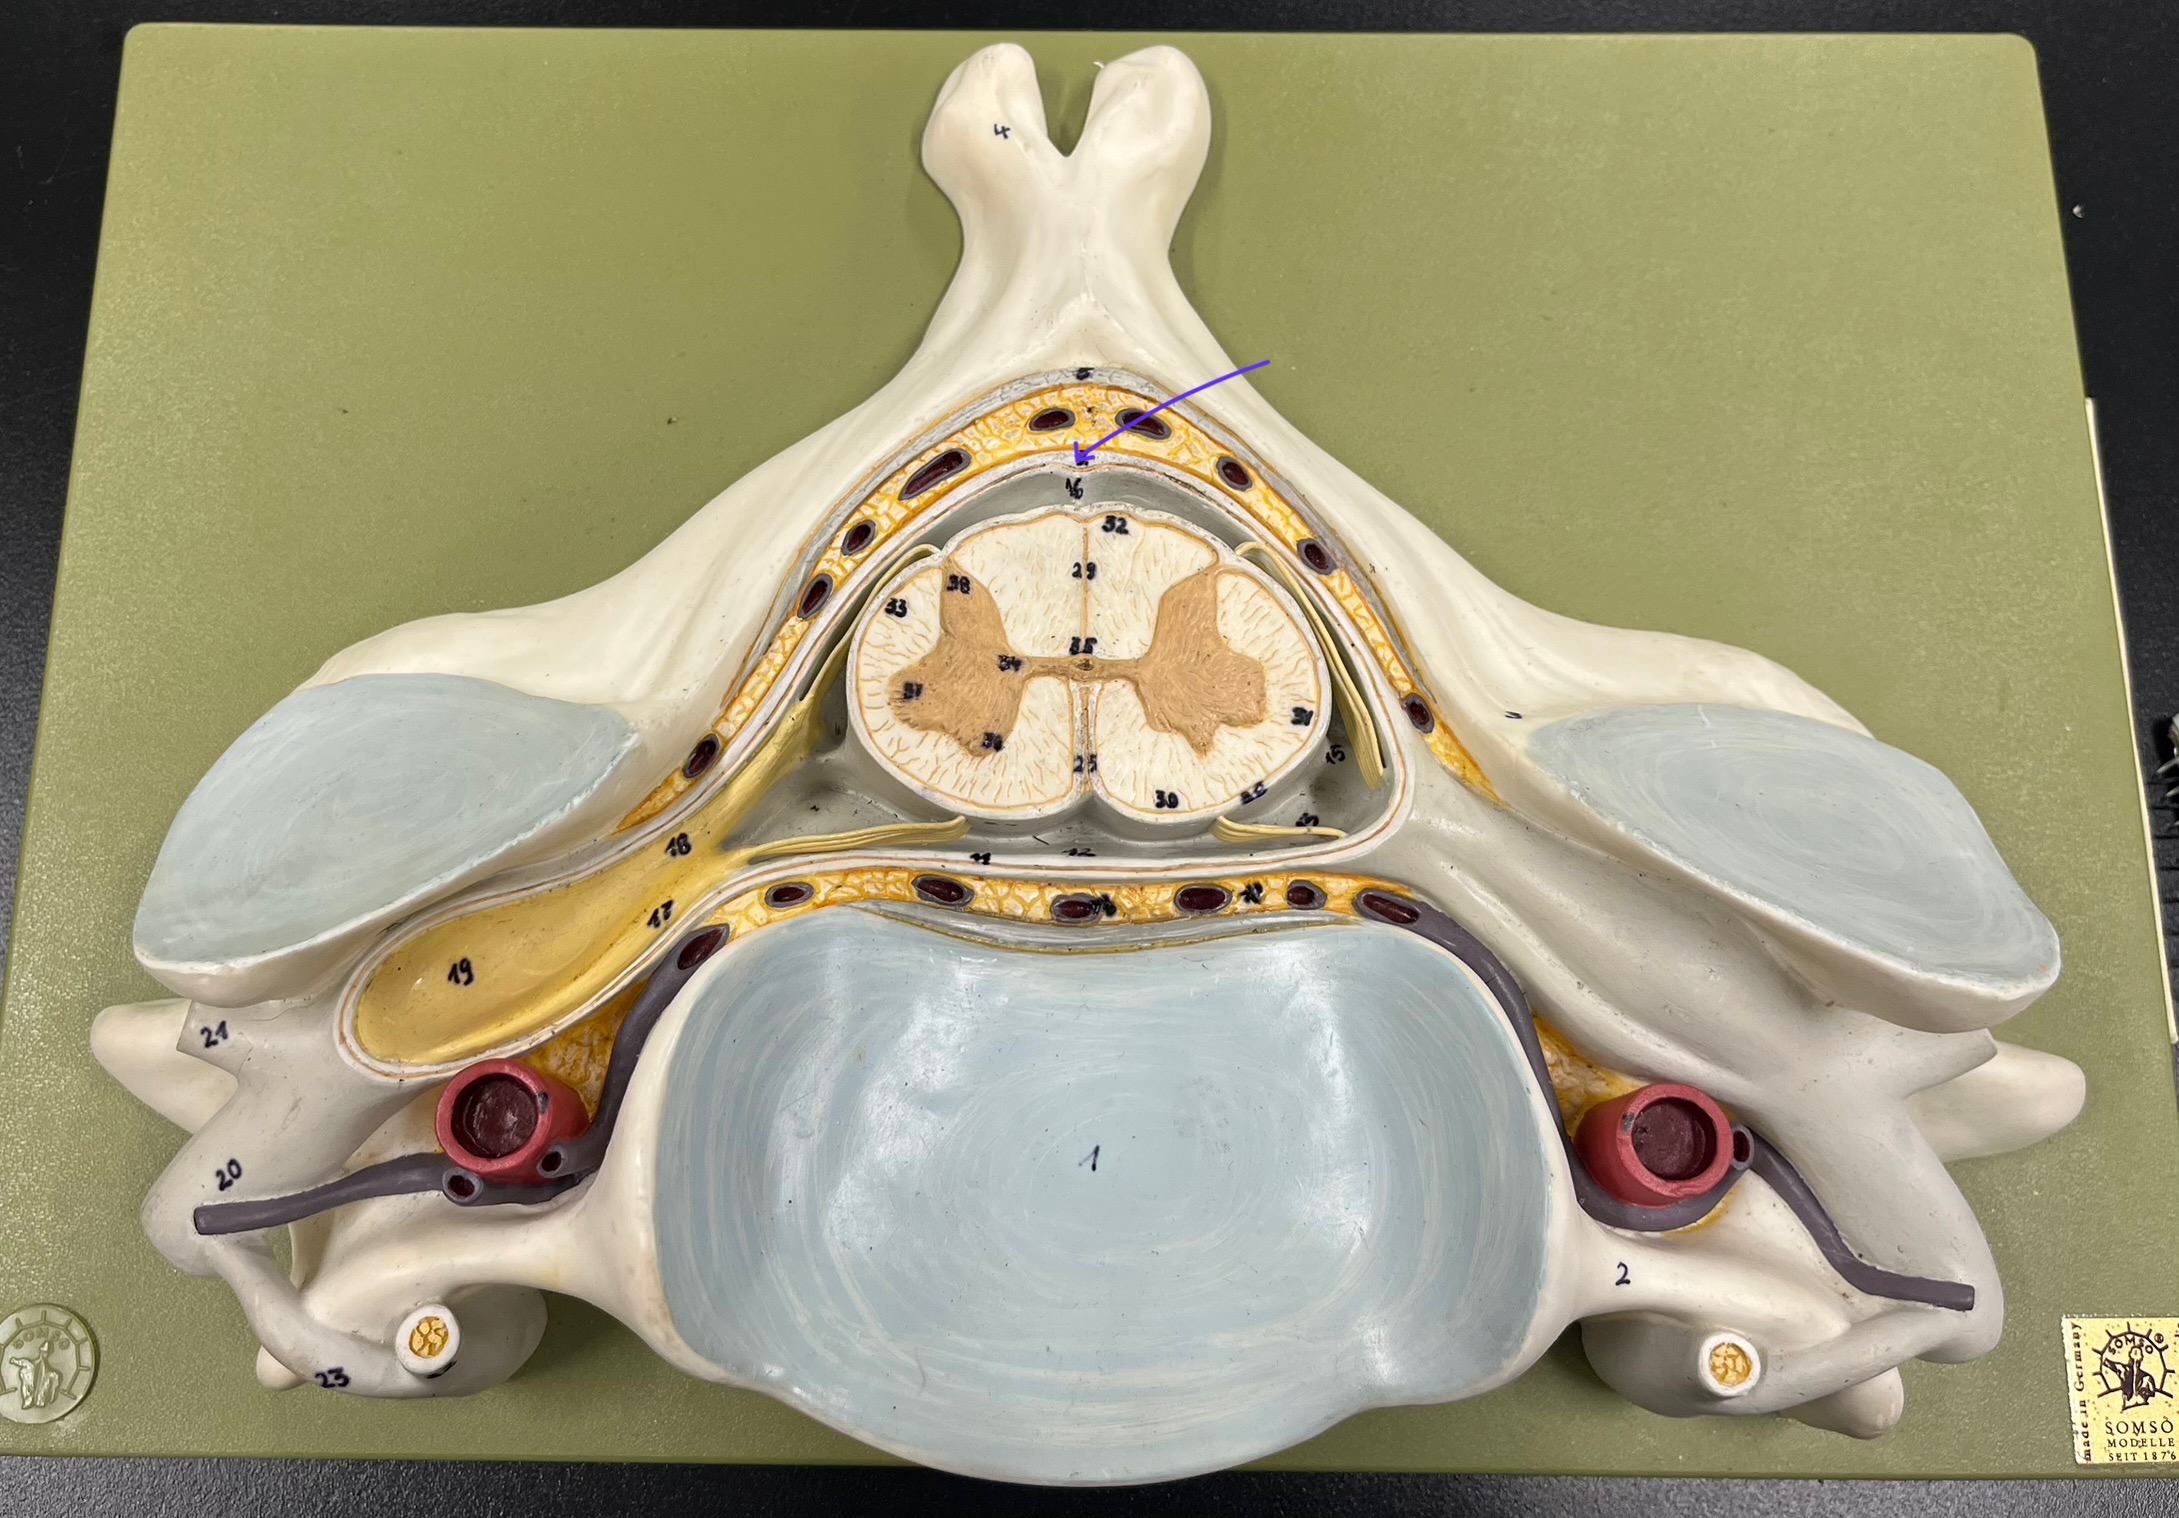

epidural space

dura mater

subdural space

arachnoid mater

subarachnoid space

pia mater

denticulate ligaments

What is the groove here?

anterior median fissure

posterior median sulcus

posterior (dorsal) horn

posterior (dorsal) horn; R—>L

anterior (ventral) horn

lateral horn (selected models)

gray commissure

central canal

anterior column

lateral column

posterior column

white commissure

posterior (dorsal) root ganglion

What is the bulb here?

posterior (dorsal) root ganglion

posterior (dorsal) root

posterior (dorsal) root

anterior (ventral) root

anterior (ventral) root

dorsal ramus

dorsal ramus

ventral ramus

ventral ramus

rami communicantes

rami communicantes

sympathetic chain ganglia

sympathetic chain ganglia